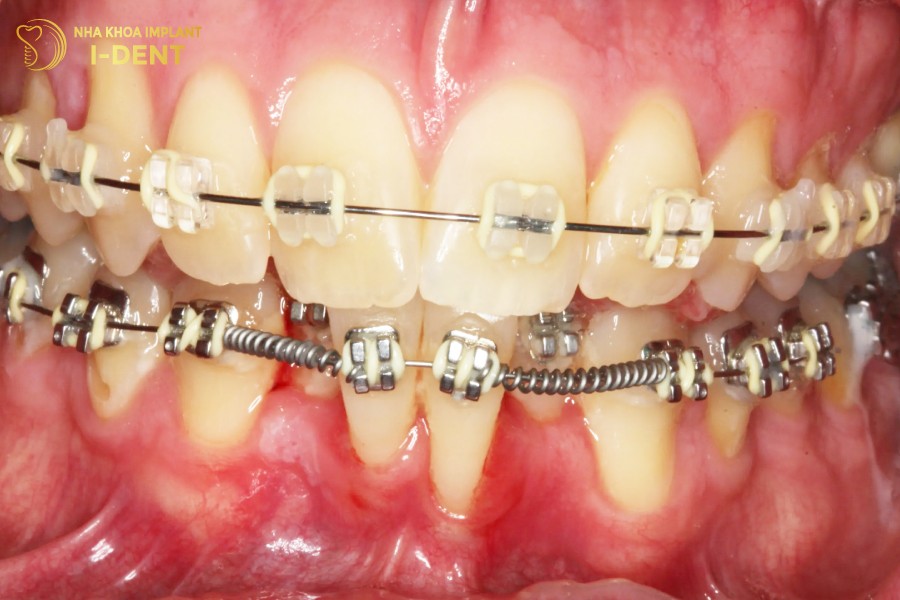

Tác động của tiêu xương răng thường diễn ra sau một thời gian niềng răng. Xương răng, được tạo thành từ muối khoáng sinh học, dễ bị suy giảm về chiều cao, mật độ và thể tích khi chịu tác động bên ngoài. Điều này có thể xảy ra theo chiều dọc hoặc chiều ngang tùy thuộc vào cơ địa của mỗi người.

Sau khoảng 3 tháng niềng răng, sự suy giảm về mật độ xương hàm trở nên rõ rệt. Răng liền kề có thể dần dần di chuyển về vị trí của răng đã bị mất. Trong năm đầu tiên của quá trình niềng răng, một phần xương hàm có thể bị tiêu xương. Khi ấy, bạn sẽ thấy những dấu hiệu như má hóp, nướu bị lõm sâu,…

Tiêu xương khi niềng răng

Tuy nhiên, tiêu xương khi niềng răng chỉ xảy ra nếu thực hiện niềng răng tại các cơ sở kém chất lượng. Hoặc do một trong số nguyên nhân sau đây:

- Tay nghề của bác sĩ: Bác sĩ giữ vai trò quan trọng quyết định kết quả niềng răng. Nhưng nếu tay nghề bác sĩ kém, lực siết răng không đồng đều hoặc không phù hợp có thể gây tổn thương gây tiêu xương.

- Bệnh lý răng miệng chưa được điều trị: Viêm nha chu và các bệnh lý khác có thể gây tổn thương cho xương hàm và mô nướu, ảnh hưởng đến quá trình niềng răng.

- Quá trình dịch chuyển răng chậm: Nếu sự dịch chuyển diễn ra chậm, việc bồi thường canxi cho xương hàm cũng chậm, dẫn đến suy giảm mật độ khoáng.

- Chăm sóc răng miệng không đúng cách: Các vấn đề như viêm nha chu, viêm nướu có thể gây tổn thương xương hàm, đặc biệt khi trong quá trình niềng răng.